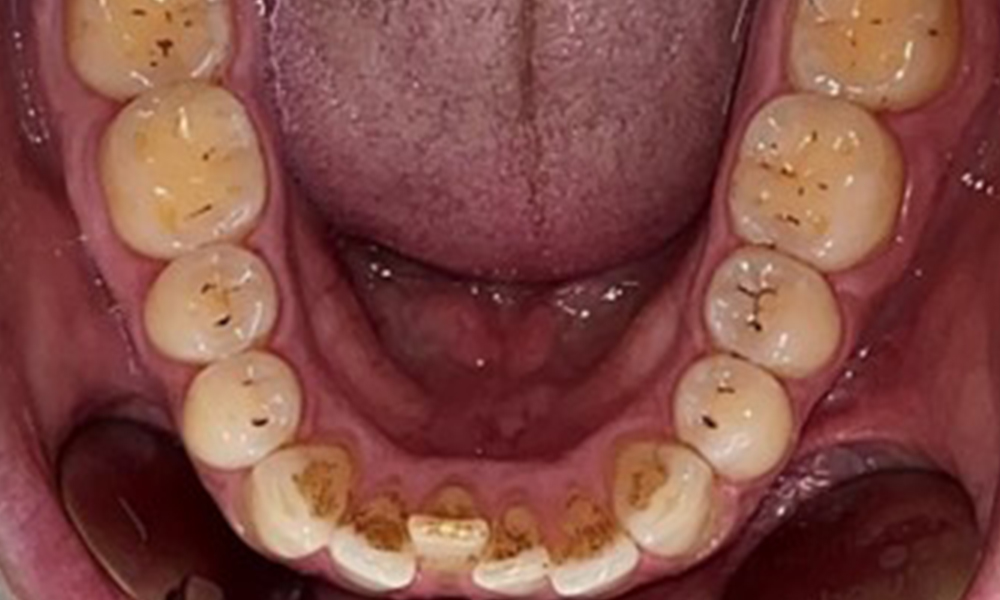

Няма патологични екстраорални резултати. По време на интраоралния преглед се установи кафеникаво оцветяване в близост до кератинизираната гингива и при прехода към подвижната лигавица (фиг. 2), което може да се отдаде на консумацията на никотин. В областта на небцето, особено в близост до небцовите повърхности на максиларните молари, се наблюдават белезникави лезии на лигавицата, които показват повишена кератинизация и също могат да се припишат на консумацията на никотин. Езикът е покрит с бяло-кафеникаво покритие, което може да се отстрани.

Дентални резултати

Пациентът има пълно съзъбие с общо 28 зъба. Налице са забележими ерозии и атриции. (Фиг. 4, Фиг. 5). Поради бруксизъм пациентът е носил шина с коригиран блок на захапката през нощта в продължение на много години. Ерозиите са причинени от продължителна консумация на изотонични напитки. Не сe наблюдава загуба на пародонтална кост или активни кариозни лезии.

Инструкциите и мотивацията са важни компоненти на тези срещи. Доброто поведение и разбиране на оралната хигиена в домашни условия са важни за пациентите. Натрупването на зъбна плака е особено видимо в цервикалните области (фиг. 8).